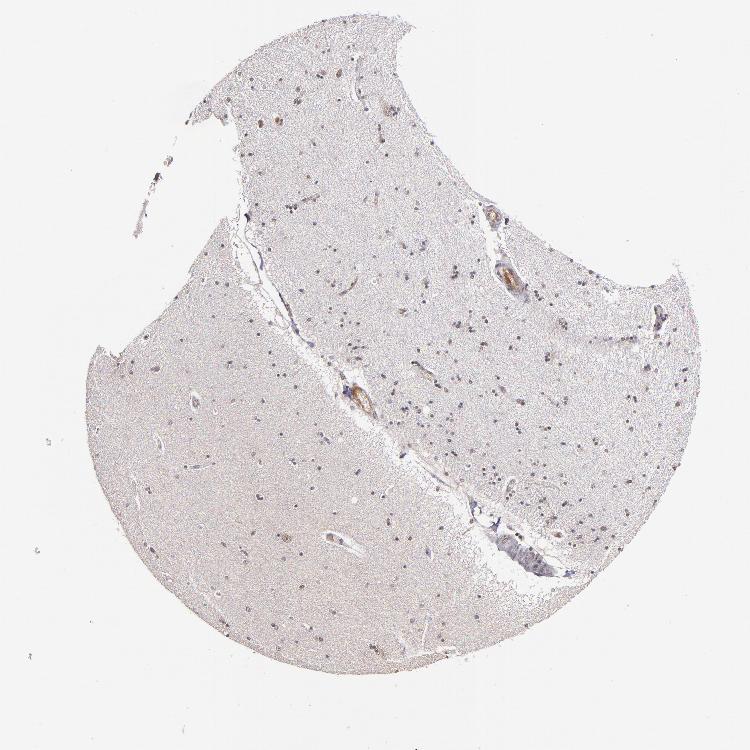

HIPPOCAMPUS - Antibody stainingi

Antibody staining in the annotated cell types in the current human tissue is reported as not detected, low, medium, or high, based on conventional immunohistochemistry profiling in selected tissues. This score is based on the combination of the staining intensity and fraction of stained cells.

Each image is clickable and will lead to virtual microscopy that enables deeper exploration of all samples and also displays staining intensity scores, fraction scores and subcellular localization as well as patient and tissue information for each sample.

Antibody HPA003128Antibody HPA004112Antibody CAB000146

Glial cells MediumMediumLow

Neuronal cells MediumMediumNot detected